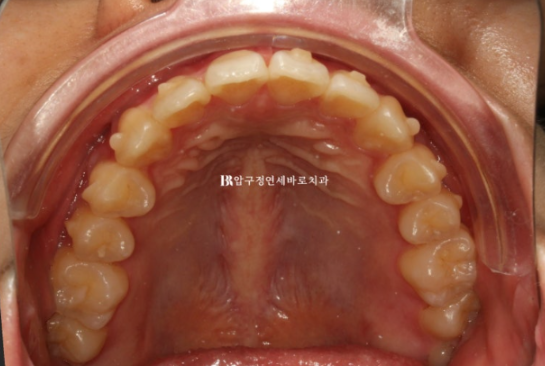

24년 3월부터 24년 4월까지 두달간 첫세트 7개의 장치를 다 낀 모습입니다.

24.04

앞니 배열은 97%정도 완료가 되었습니다.

미세하게 덜 돌아간 치아드로가 미세한 공간들을 마무리 하기 위해 추가제작 즉 재제작에 들어갑니다.